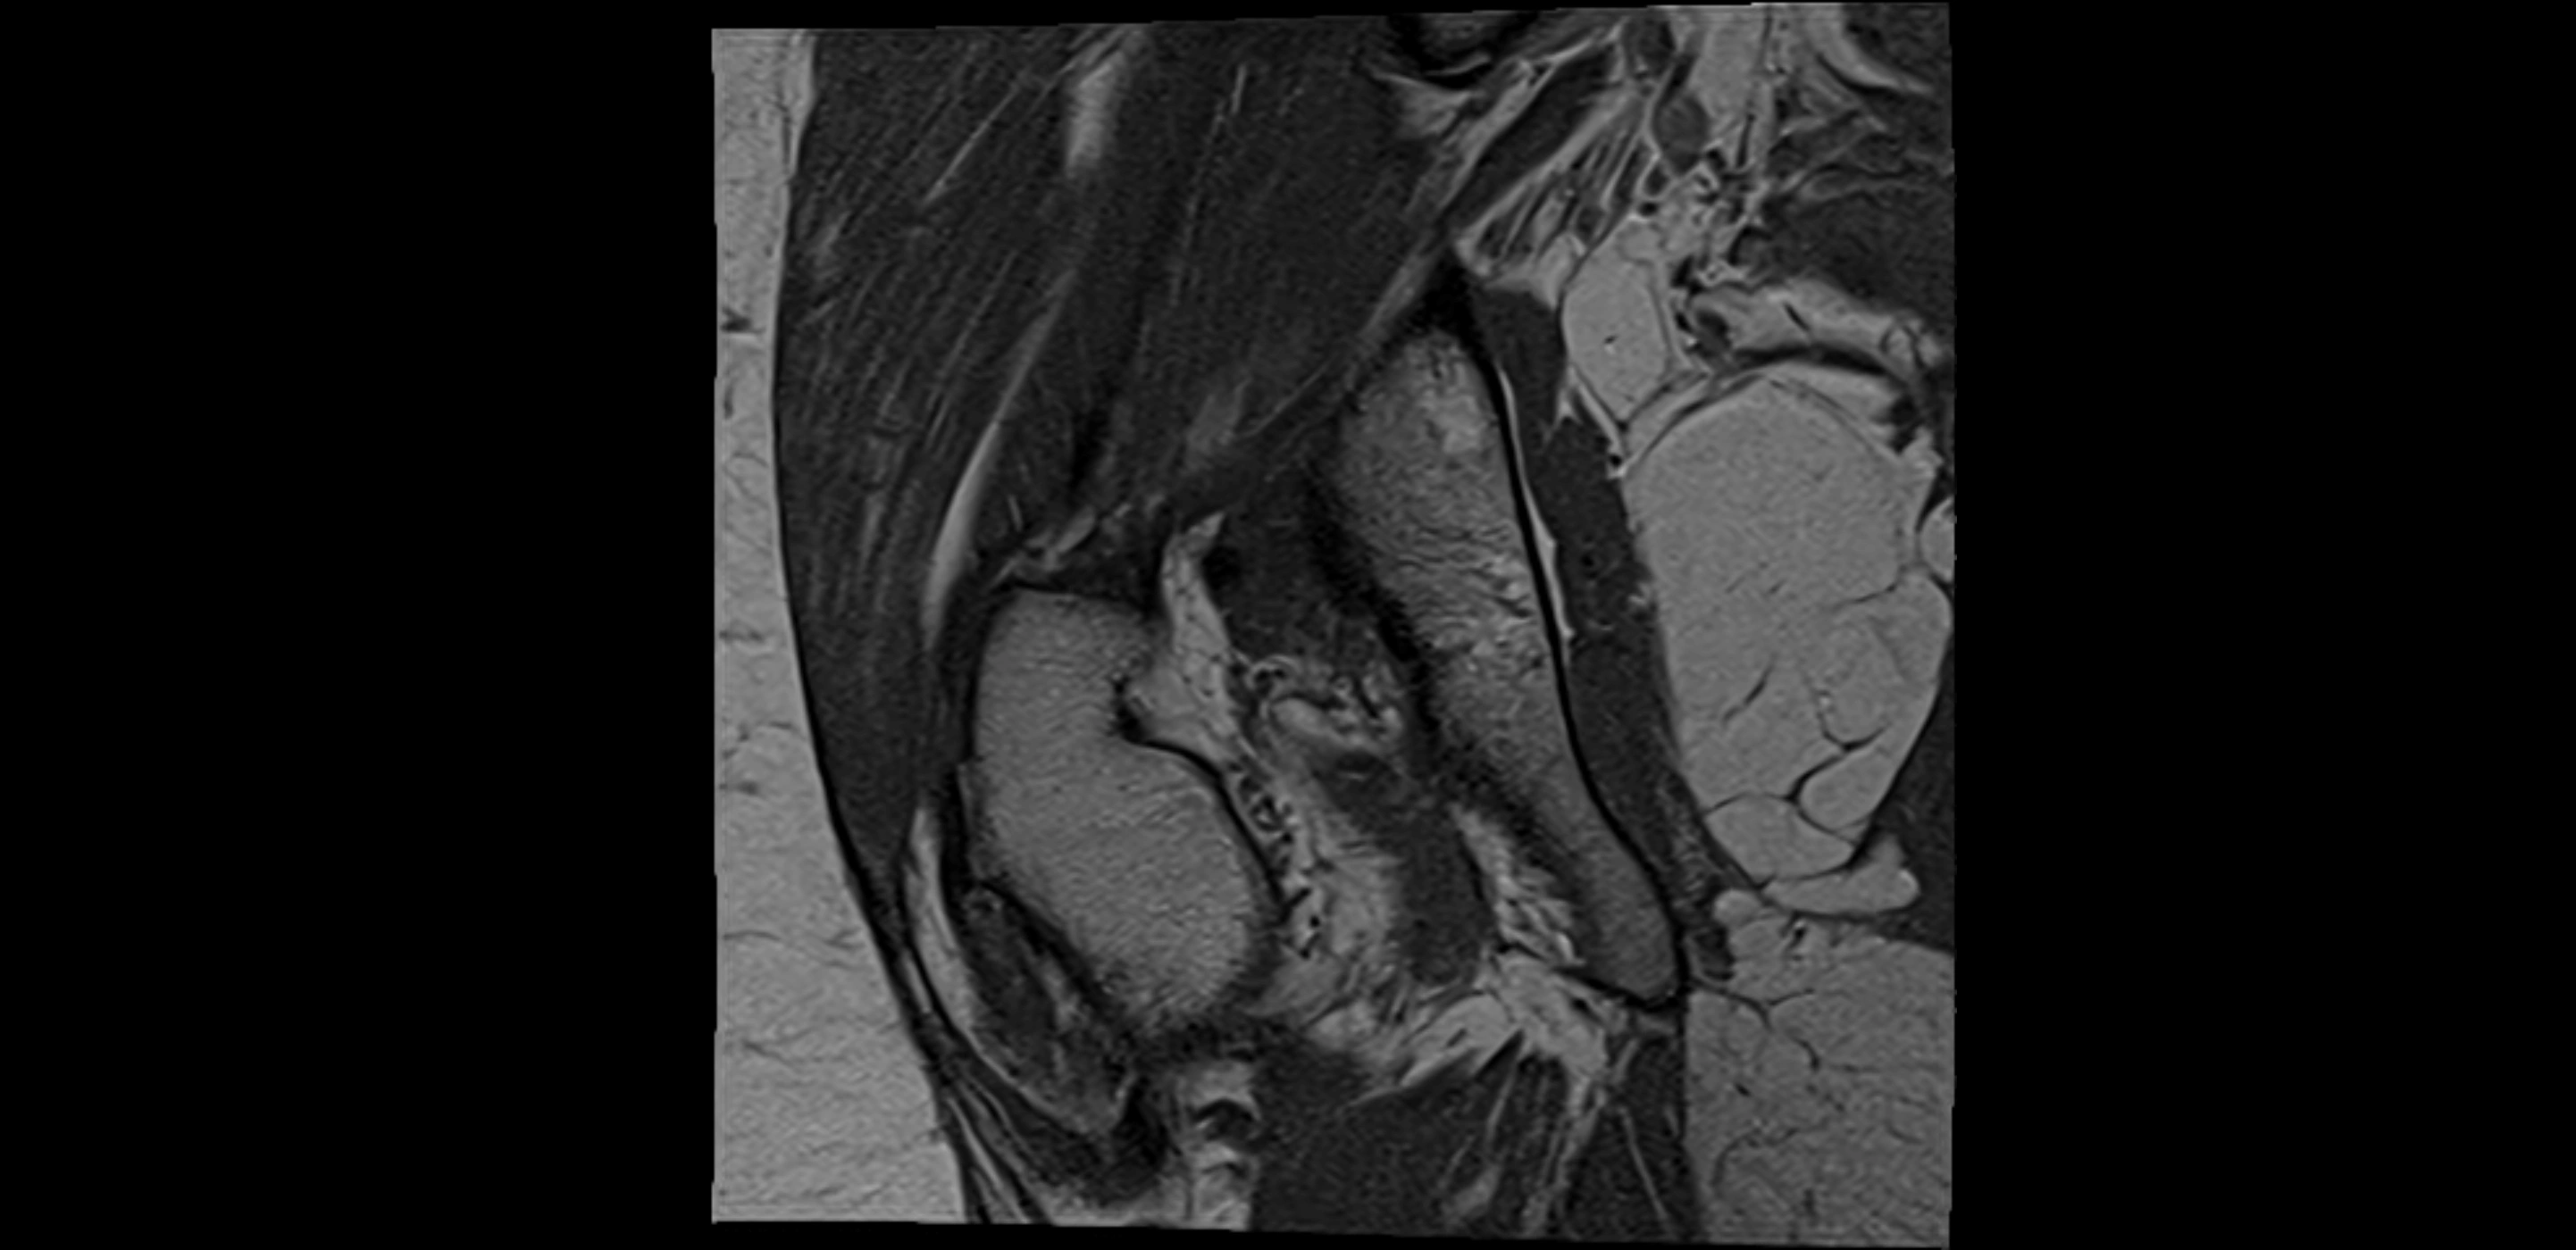

MRI Appearance

T1-weighted images:

• Labrum: low signal intensity (dark)

• Surrounded by intermediate signal joint fluid (bright on arthrogram)

• Tears: linear or focal areas of intermediate-to-high signal interrupting labral continuity

T2-weighted images:

• Joint fluid: bright, making labral tears visible as fluid extending into or around labrum

• Degeneration: may show areas of increased signal within labrum

MRI image

image